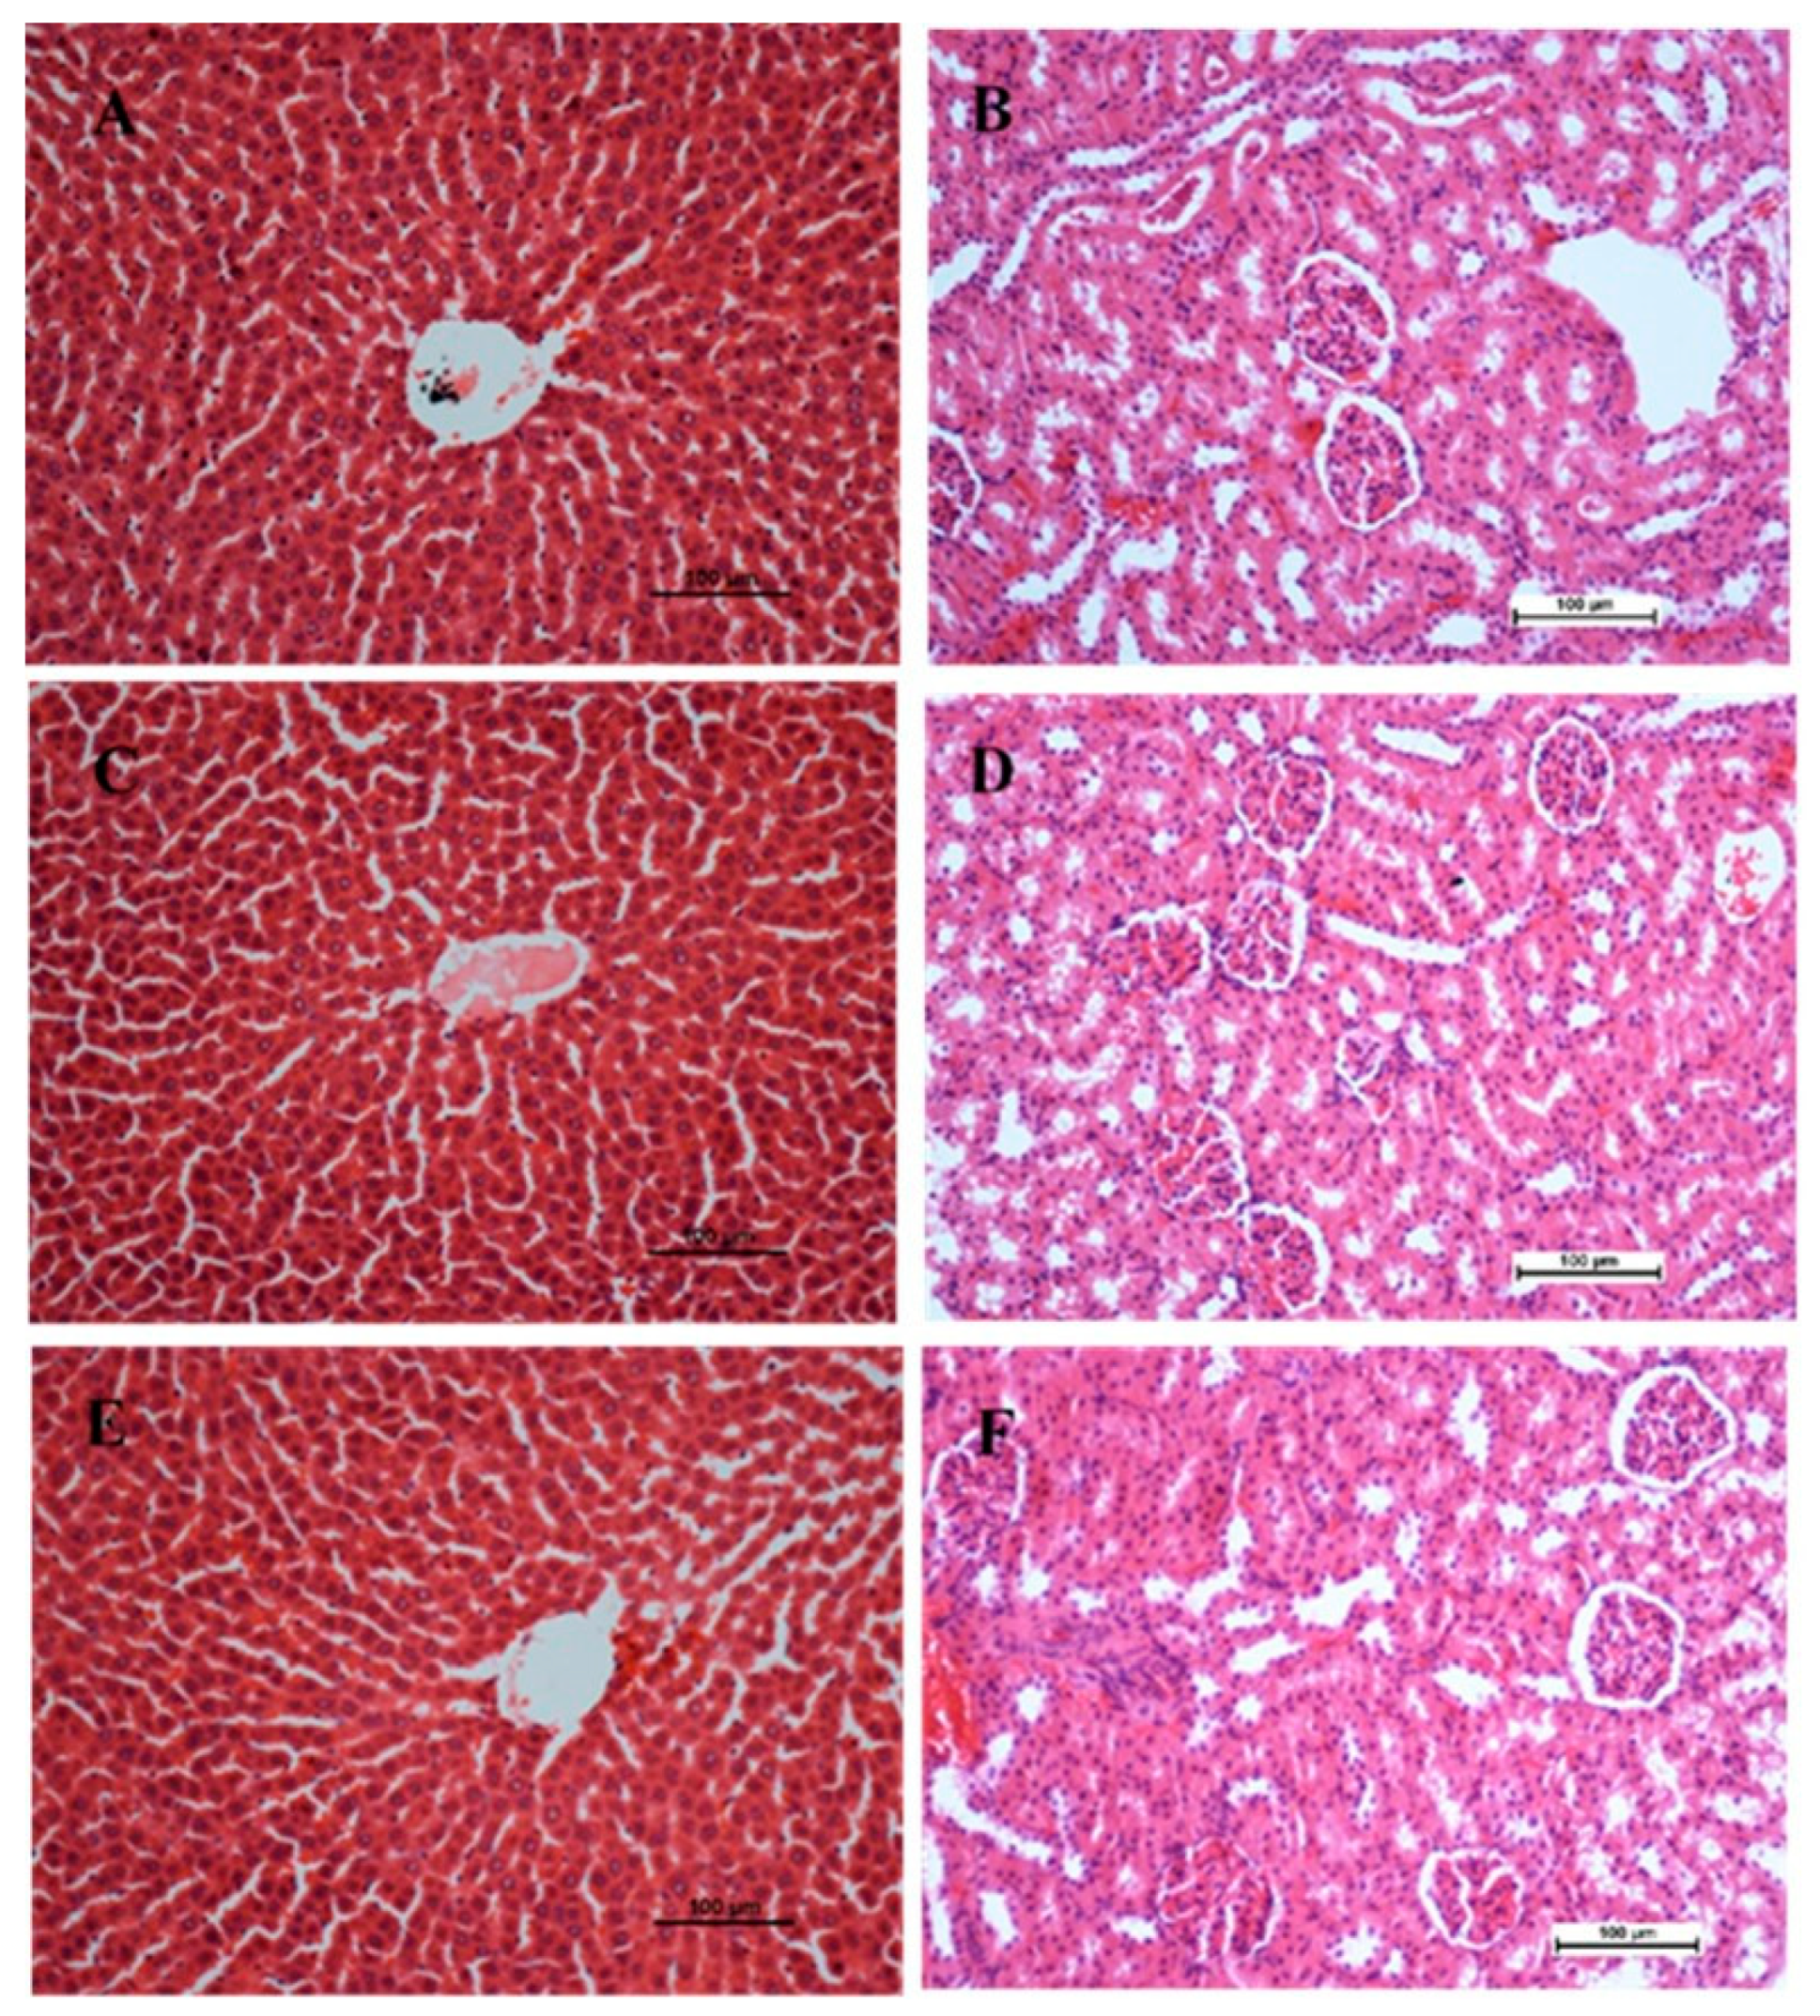

2.3. Gross and Histopathological Examinations of the Liver

4.8. Gross and Histopathology Studies